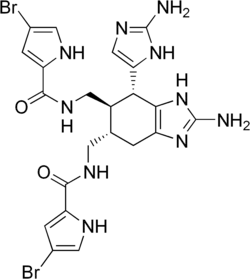

Размножаются половым и бесполым путями (в том числе с образованием покоящихся почек — геммул). Обладают высокой способностью к регенерации. Многие губки, а также населяющие их микроорганизмы вырабатывают биологически активные вещества, используемые в медицине.

| Обыкновенные губки | Морские, пресные (около 80—90 % всех известных видов губок)[144] | От приливной зоны до абиссали;[86] хищные обыкновенные губки могут быть найдены на глубине 8840 м[81] | Любые |

Губковые рифы и сообщества

Особым видом рифов являются губковые рифы[145]. Подобные рифы ранее были широко распространены в истории Земли[146]. Наиболее ранние из них датируются среднем триасом (245—208 млн лет назад), а своего наибольшего процветания они достигли в конце юрского периода (208—146 млн лет назад). В это время система губковых рифов, образованная преимущественно шестилучевыми губками и имеющая длину около 7 тысяч км, пересекала поперёк северный бассейн древнего океана Тетис; она является наиболее крупной среди известных конструкций, созданных когда-либо живыми организмами. Резкое сокращение количества губковых рифов произошло в меловом периоде на фоне всё возрастающего доминирования коралловых рифов[147].

Мелководные губковые рифы ныне отсутствуют, и все известные подобные рифы являются глубоководными[148]. Современные губковые рифы нуждаются в уникальных условиях существования, которые могут объяснить их редкость. Они возникают в желобах континентального шельфа, в местах с оптимальными для их развития условиями: со сравнительно низкой скоростью осадконакопления, с высокими скоростями течения[146], высокой концентрацией в воде диоксида кремния и низкой концентрацией кислорода, со стабильным морским дном, состоящим из камней, крупного гравия и крупных валунов, при температурном режиме воды 5,5-7,3 °C[147]. Губковые рифы в настоящее время известны на западе Канадского континентального шельфа[149], широко распространены в Северной Атлантике, в канадской Арктике и на континентальном шельфе в Антарктике[148]. Сформированный кремниевыми губками (Demospongiae) риф существует в Северном Ледовитом океане у острова Аксель-Хейберг[150]. Четыре рифа, образованные шестилучевыми губками в заливе Королевы Шарлотты на расстоянии 70-80 км от береговой линии и на глубине 165—240 м, занимают площадь 700 км² морского дна[148]. Некоторые губки из рода Heterochone в северной части Тихого океана могут создавать рифы высотой более 20 м, простирающиеся на несколько километров. Также вдоль глубоководных коралловых рифов обычно тянется зона обломков кораллов, в которой доминируют губки, среди которых имеются виды, разрушающие мёртвые кораллы[151]. В юго-западной части Баренцева моря имеются глубоководные сообщества губок и плеченогих[146].

Взаимоотношения с другими организмами

Симбиотические ассоциации

Губки могут вступать в симбиотические отношения с представителями большинства групп организмов[152]: с водорослями[153], грибами[154], прокариотами[155] и др.

Представители типа Porifera предоставляют среду обитания для многих одноклеточных и многоклеточных организмов. Многоклеточные организмы обычно выступают комменсалами и поселяются на поверхности тела губки и в её внутренних полостях, не мешая её жизнедеятельности[156]. Среди эндобионтов губок отмечены стрекающие, турбеллярии, немертины, сипункулиды, полихеты, моллюски, ракообразные, многоколенчатые, иглокожие, асцидии и рыбы[157].

Одноклеточными симбионтами губок могут быть динофлагелляты, зоохлореллы, красные водоросли, нитчатые зелёные водоросли, а также грибы[156]. Пресноводные губки наиболее часто находятся в симбиотических отношениях с различными водорослями, которые обусловливают их зелёную окраску[26].

Губки, в которых поселяются фотосинтезирующие эндосимбионты, выделяют в три раза больше кислорода, чем поглощают, а также продуцируют больше органического вещества, чем потребляют. Такая роль губок в образовании первичной продукции особенно важна в австралийском Большом Барьерном рифе, но в Карибском море она не столь велика[158].

Однако особенно важными симбионтами губок являются облигатные видоспецифичные автотрофные или неавтотрофные прокариоты (бактерии и археи), которые поселяются в мезохиле. Взаимодействие между губками и этими микроорганизмами может происходить по-разному. Уникальность симбиоза губок с прокариотами заключается в том, что все исследованные к настоящему времени виды губок имеют симбиотические ассоциации с одним или более видами бактериальных симбионтов[155][159][160][161].

Прокариотические симбионты, как правило, располагаются между элементами мезохила и физически отделены от воды пинакодермой. Однако известны губки, у которых симбионты внутриклеточные: они локализованы в специальных клетках — бактериоцитах[162]. Биомасса прокариотических эндосимбионтов может быть весьма значительной и составлять до 40 % (и даже до 60 %) массы губки-хозяина, а концентрация бактериальных симбионтов в губке может на 2-3 порядка превышать концентрацию прокариотических организмов в окружающей водной среде[163]. Прокариоты могут проникать в тело губки двумя путями: из воды в окружающей среде, или же путём вертикального переноса от материнской губки к следующему поколению через яйца или личинки; возможность вертикального переноса прокариотических симбионтов говорит об их исключительной важности для жизни губок. Губкам удаётся поддерживать разнообразные, но в то же время специфичные микробные сообщества внутри себя — несмотря на то, что вместе с током воды при фильтрационном питании в их тела проникает множество морских микроорганизмов[164].

Внутри губок поселяются прокариоты самого разнообразного систематического положения, относящиеся примерно к 20 бактериальным филам, причём представители одной филы — Poribacteria — встречаются исключительно в губках. Симбиотические прокариоты могут принимать участие в разнообразных физиологических процессах губок — например, в круговороте нерастворимых белков и структурных перестройках органического скелета и внеклеточного матрикса. Многие прокариоты-симбиоты синтезируют антибиотики и вещества с резким запахом, отпугивающим хищников. Они также могут служить дополнительным источником питания губок, причём могут поглощаться как сами прокариоты путём фагоцитоза, так и продукты их жизнедеятельности[165]. Можно сказать, что губка-хозяин и населяющие её микроорганизмы метаболически связаны и обмениваются соединениями азота, продуктами фиксации СО2, вторичными метаболитами и полученными из воды органическими соединениями[164]. Например, внутри губки Lophophysema eversa живут автотрофные микроорганизмы, способные окислять аммоний, нитрит и сульфид и потому играющие важную роль в круговороте углерода, азота и серы в теле губки. Кроме того, они нейтрализуют токсичные для губки-хозяина аммоний, нитрит и сульфид[166].

Губки вступают в разнообразные взаимоотношения с другими животными. Например, довольно крупная губка Lissodendoryx colombiensis, живущая на каменистых субстратах, может также заселять заросли морских трав. При этом она позволяет окружать и обрастать себя губкам, живущим в морских травах и опасным для местных морских звёзд; таким образом, Lissodendoryx colombiensis обеспечивает себе защиту, а губки зарослей морских трав получают возможность жить на некотором поднятии относительно морского дна[167].

Особенным разнообразием отличаются взаимоотношения между ракообразными и губками[26]. Многие виды мелких веслоногих и равноногих рачков, бокоплавов сожительствуют или паразитируют в губках. Часто десятиногие раки и креветки используют губок в качестве убежища от врагов. Креветки рода Synalpheus из семейства Alpheidae образуют колонии внутри губок, причём каждый вид креветок населяет только определённый вид губок; благодаря этому род Synalpheus является одним из самых многочисленных родов ракообразных. Вид Synalpheus regalis использует губок не только для питания, но также для защиты от других креветок и хищников. В одной губке может жить 16 тысяч особей креветок, питающихся самыми крупными частицами, попадающими внутрь тела губки при фильтрационном питании[168][169]. В другом семействе креветок — Spongicolidae — практически все представители являются облигатными симбионтами глубоководных стеклянных губок (только в роде Microprosthema известны свободноживущие формы)[170]. В частности, самец и самка из рода Spongicola поселяются в полости стеклянной губки Euplectella oweni на стадии личинки, а во взрослом состоянии выйти за остов губки уже не могут[26].

_-_NHM_London_-_With_sponge.jpg)

Непривлекательность губок для хищников часто используют некоторые крабы (например, Dromia personata), которые носят на себе куски губок, поддерживая их задней парой своих конечностей. Со временем губка приобретает форму панциря[171][172]. Острорылый краб Oregonia gracilis прикрепляет губок, водоросли и сидячих животных к своему панцирю, так что на его спине образуется микросообщество, маскирующее краба[173]. 13 видов раков-отшельников могут образовывать симбиоз в форме комменсализма с пробковой губкой (Suberites domuncula)[174]. Последняя селится на пустой раковине брюхоногого моллюска, и в этой же раковине поселяется рак-отшельник. Со временем вся раковина обрастает губкой; внутри последней образуется спиральная полость, в которой живёт рак-отшельник[26].

Некоторые животные используют в качестве защиты отдельные иглы губок, в массе откладывающиеся после их гибели на дне. Эти животные сооружают свои домики частично или полностью из спикул и игл губок (фораминиферы, некоторые черви, голотурия Pseudostichopus trachus и др.)[26].

Иногда на губках могут поселяться сидячие, прикреплённые животные, к числу которых относятся различные усоногие раки (в частности, балянусы). На корневом пучке игл ряда видов стеклянных губок часто встречаются морские уточки, а также могут селиться колониальные кораллы (Palythoa). На некоторых губках (Axinella) постоянно поселяется корковая актиния (Parazoanthus axinellae)[26].